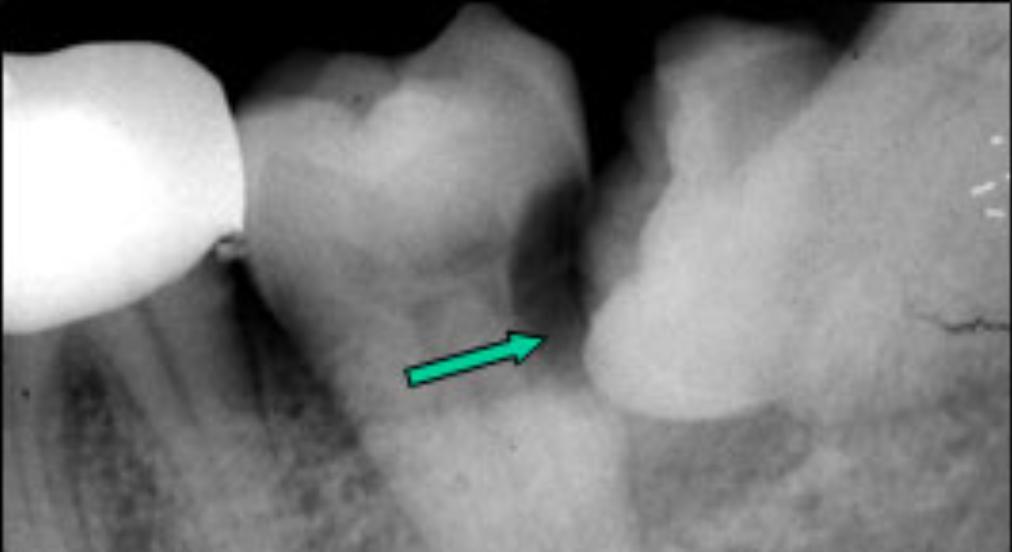

很多时候智齿的生长会和前牙形成一个夹角,形成一个空间。食物往往会嵌塞其中,让您感到不适。长期的食物嵌塞不光会导致牙龈的红肿、退缩,甚至可以是牙槽骨吸收,形成恶性循环,加重食物嵌塞。

4)根、骨吸收:

由于智齿生长持续的压力压迫,导致邻近牙齿、骨质的吸收。可导致邻牙不适、疼痛甚至松动脱落。